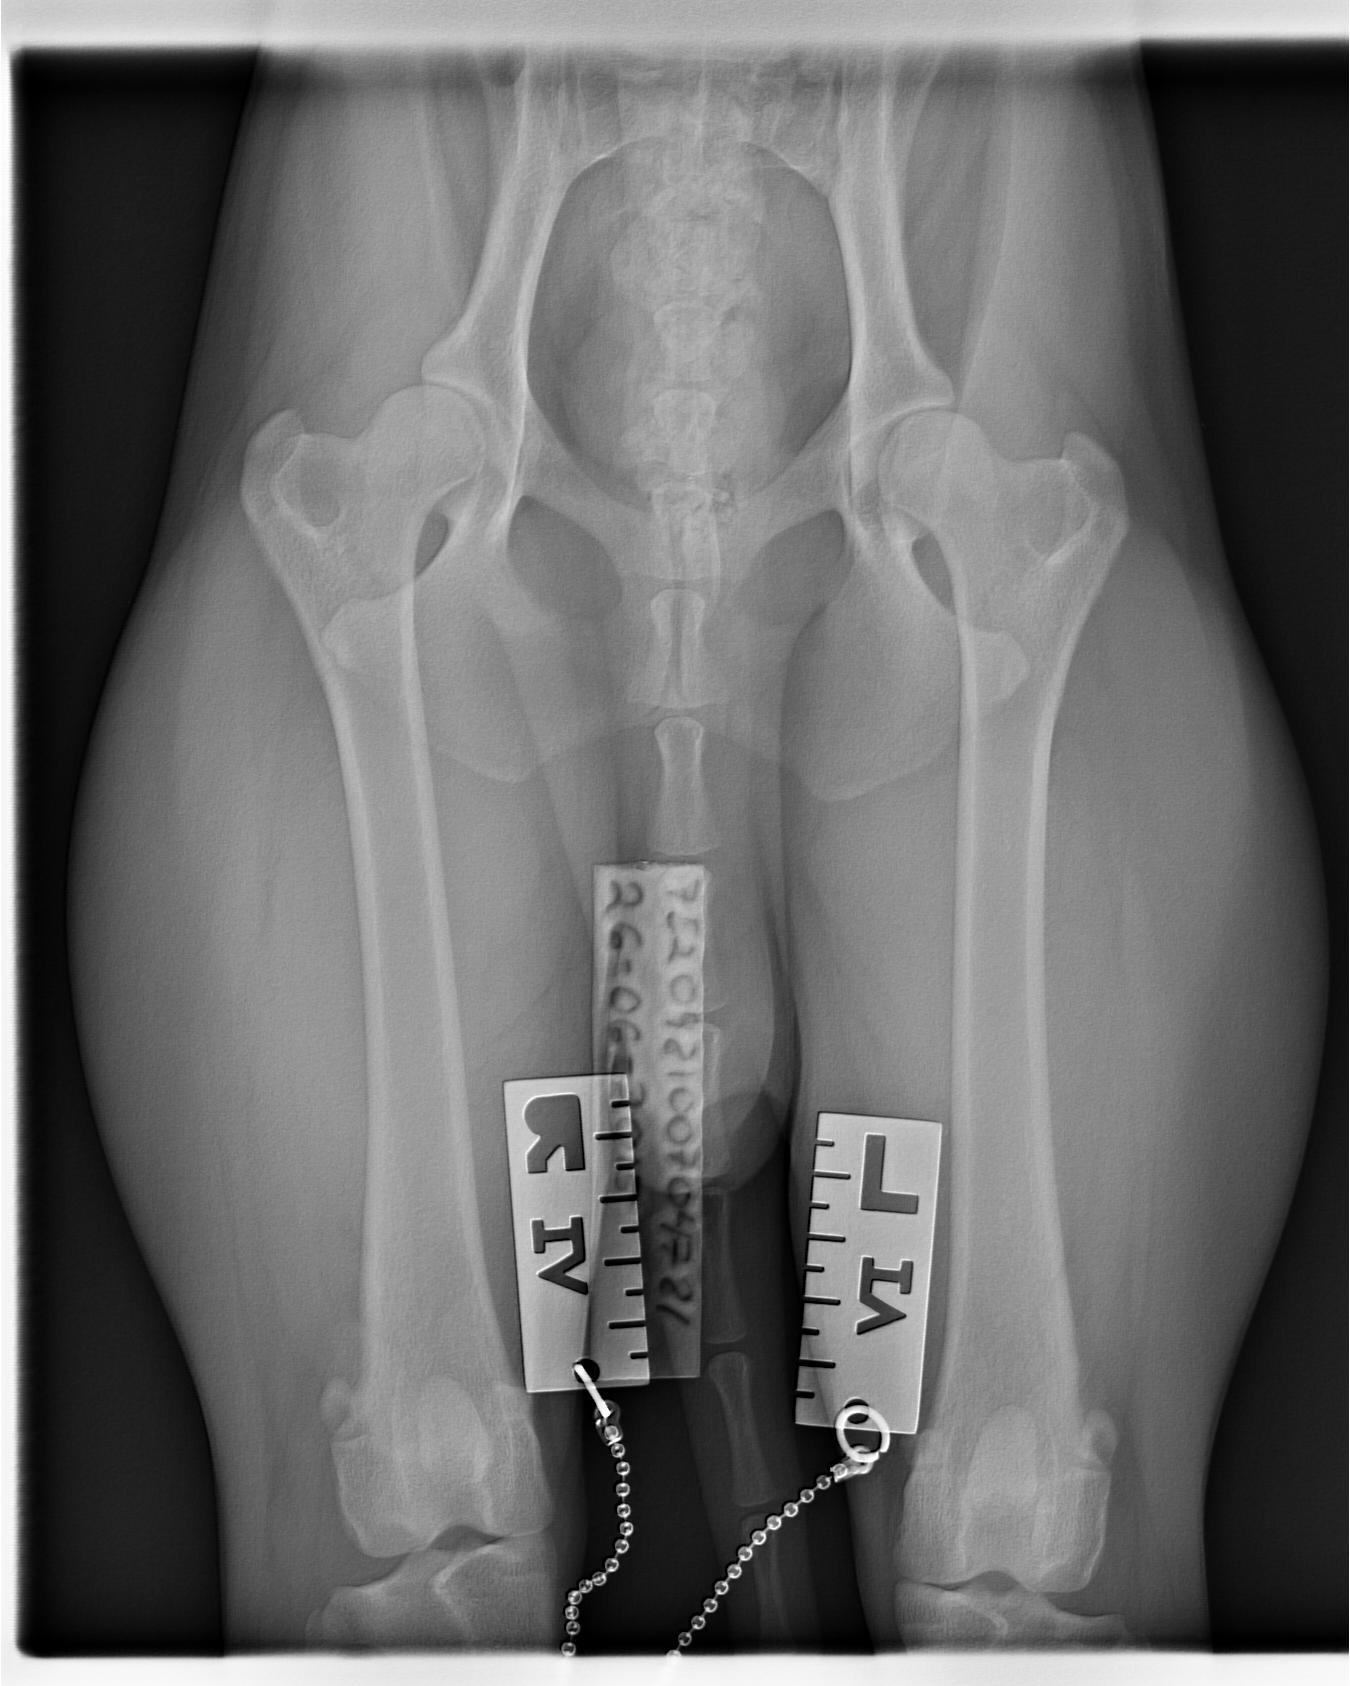

Sen sövdes han med en spruta i en muskel som han inte verkade känna och somnade mycket snabbt. Jag var med och höll i framdelen när han röntgades. Bilder togs på höfter, armbågar och rygg samt att ortopeden kände på knäna och svansen. Svansen bad jag honom känna på då den inte är helt rak i vissa lägen men han tyckte att det var så lite att det inte var något att bry sig om. Knäna var helt som de skulle så patella är UA.

När bilderna var tagna så fick Helix en uppvakningsspruta och sen gick vi och kollade på bilderna som han gick igenom väldigt noggrant. Överlag såg det helt normalt ut, något grundare skål på höger höft och en liten ”trappa” på ena armbågen, inga förändringar på leden så han trodde inte att det var något särskilt. Han kollade även på knäna på höftbilderna för att utesluta att höger knä skulle vara problem som orsakade muskelömheten men det såg helt normalt ut. Ländryggen hade rätt antal kotor och såg normal ut i övrigt.

Bilderna: